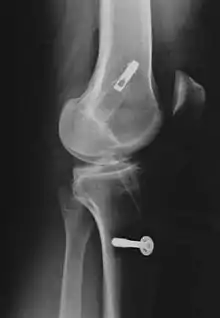

Le décollement ou l'arrachement du LCA de l'os est substantiellement plus rare que la rupture intraligamentaire[5] et n'est pas une rupture de ligament. Ce cas particulier survient plus fréquemment chez les enfants, particulièrement dans le domaine du tubercule intercondylaire du tibia, et possède en général, par refixation de l'arrachement par exemple avec des vis ou des fils métalliques, de bonnes chances de guérison complète.

Les radios n'apportent aucune contribution immédiate au diagnostic de rupture de LC. Les deux LC sont invisibles à la radio, déchirés ou non. La seule utilité de la radio ne peut servir qu'au diagnostic des complications osseuses possibles.

Pour la reconstruction du LC par transplantation autologue au moyen du tendon patellaire, une partie de celui-ci est prélevée avec des morceaux d'os aux extrémités, technique dite bone tendon bone (os tendon os), ou technique BTB. Il est tiré à travers des canaux élargis (8 à 10 mm de diamètre dans le tibia et le fémur). La longueur de chacun des blocs osseux est de 20 mm. L'ancrage le plus stable de la greffe est obtenu par fixation avec des vis d'interférence. Celui-ci est particulièrement important en vue d'une mobilisation fonctionnelle rapide.